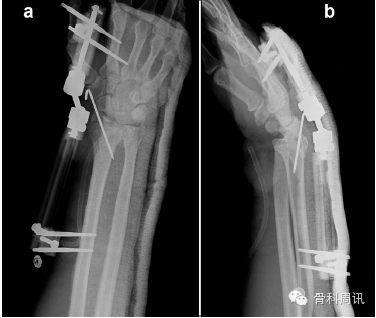

一名35歲男性從大約5米的高處墜落後,摔傷其右上肢,送往我院急診室就診。體格檢查顯示腕部銀叉樣畸形,所有手指無法正常屈伸,並且第一、二、三根手指均出現感覺喪失。橈動脈搏動不明顯。X光片顯示橈骨遠端骨折伴腕骨從尺骨遠端背側脫位(圖1)。在麻醉狀態下嚐試采取閉合複位術。複位失敗後,進行CT掃描檢查。CT顯示,橈骨莖突骨折和橈骨遠端粉碎性骨折伴腕骨背側移位和腕骨近端骨折移位。下尺橈關節顯示穩定(圖2)。由於複位失敗,所以采取手術治療。

Fig. 1. X-rays showing fracture-dislocation of distal radius, lateral (a) and AP (b)view.

圖1 X光片顯示橈骨遠端骨折脫位,側位片(a)和AP片(b)。